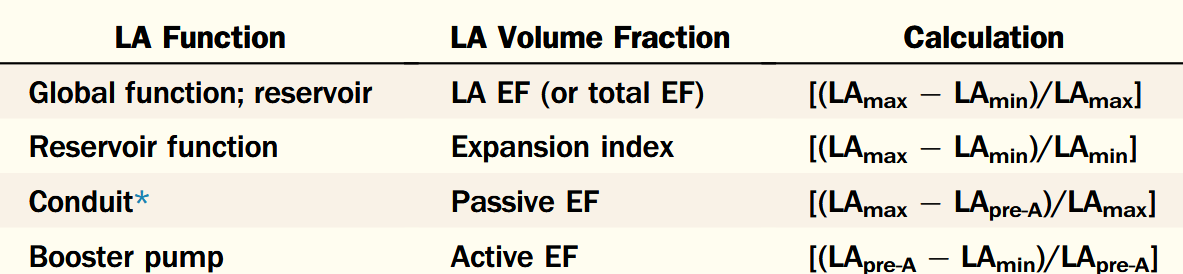

Left atrial function has been typically divided into three integrated phases: reservoir, conduit and booster-pump (Figure 1) [7–10]. Reservoir: an expansion phase during left ventricular (LV) systole; the LA stores pulmonary venous return during LV contraction and isovolumic relaxation. Conduit: the LA transfers blood passively into the LV during ventricular diastole. Booster-pump: contractile component (when supraventricular rhythm is present);